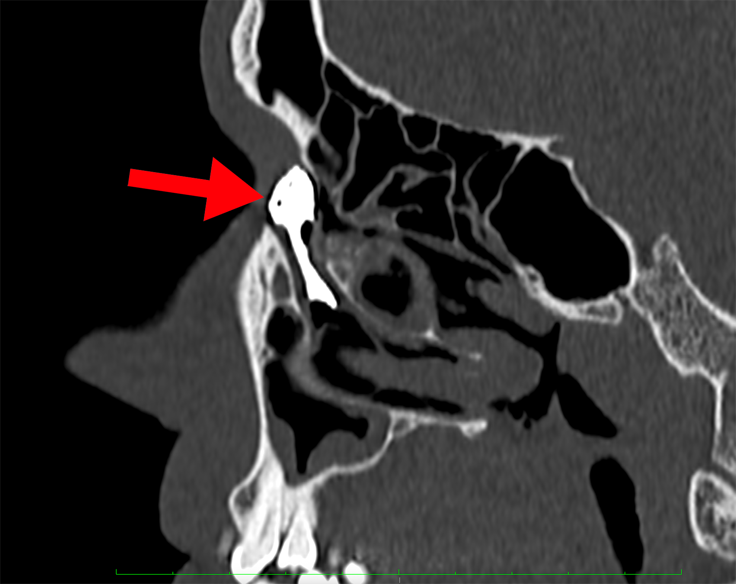

KT-DCG: zdjęcie tomografii komputerowej obszaru zatok przynosowych z kontrastowaniem dróg łzowych; czerwona strzałka wskazuje na dobrze wypełniony worek łzowy i przewód nosowo-łzowy